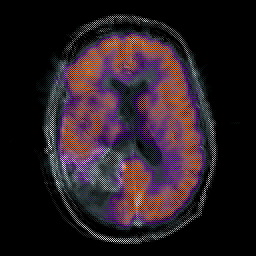

Glioma Overlay -- Slice #12

[Home][Help][Clinical] Slice 12